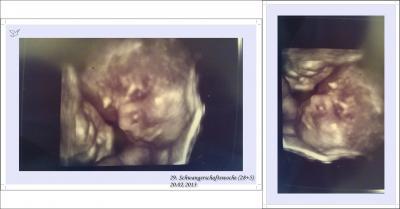

Huhu, werdende Mamis . Ich wollt' mal kurz von meinem letzten Vorsorge-Termin berichten, der am 20.02.2013 (29. Schwangerschaftswoche) war. Unserem Zwergi ging es hervorragend, er lag bereits mit dem Köpfchen nach unten. Der Bauchumfang war zu diesem Zeitpunkt schon stolze 107cm . Wir haben auch, im übrigen schon zum zweiten Mal in der gesammten Schwangerschaft, 3D/4D Ultraschall machen lassen . Der kleine Mann hat dabei kräftig gestrampelt & geboxt, wir waren soo entzückt von ihm - besonders aber von seinen vollen Lippen, die man auf dem Foto deutlich erkennen kann. Er sieht schon jetzt aus wie sein Papa, nur eben noch ohne Haare auf dem Köpfchen . Meinen nächsten Termin hab' ich nächste Woche Mittwoch. Da wird auch zum allerersten Mal CTG gemacht - ich bin schon gespannt .

Klingt toll!! und super Bilder! Da kann man echt super das kleine Gesichtchen erkennen. Und das tolle an den 3D-Bildern ist, dass die Kids tatsächlich so aussehen, wenn sie dann kommen. Das ist wirklich der Wahnsinn, wie weit wir schon mit der Technologie fortgeschritten sind und so tolle Bilder bekommen können!! :)